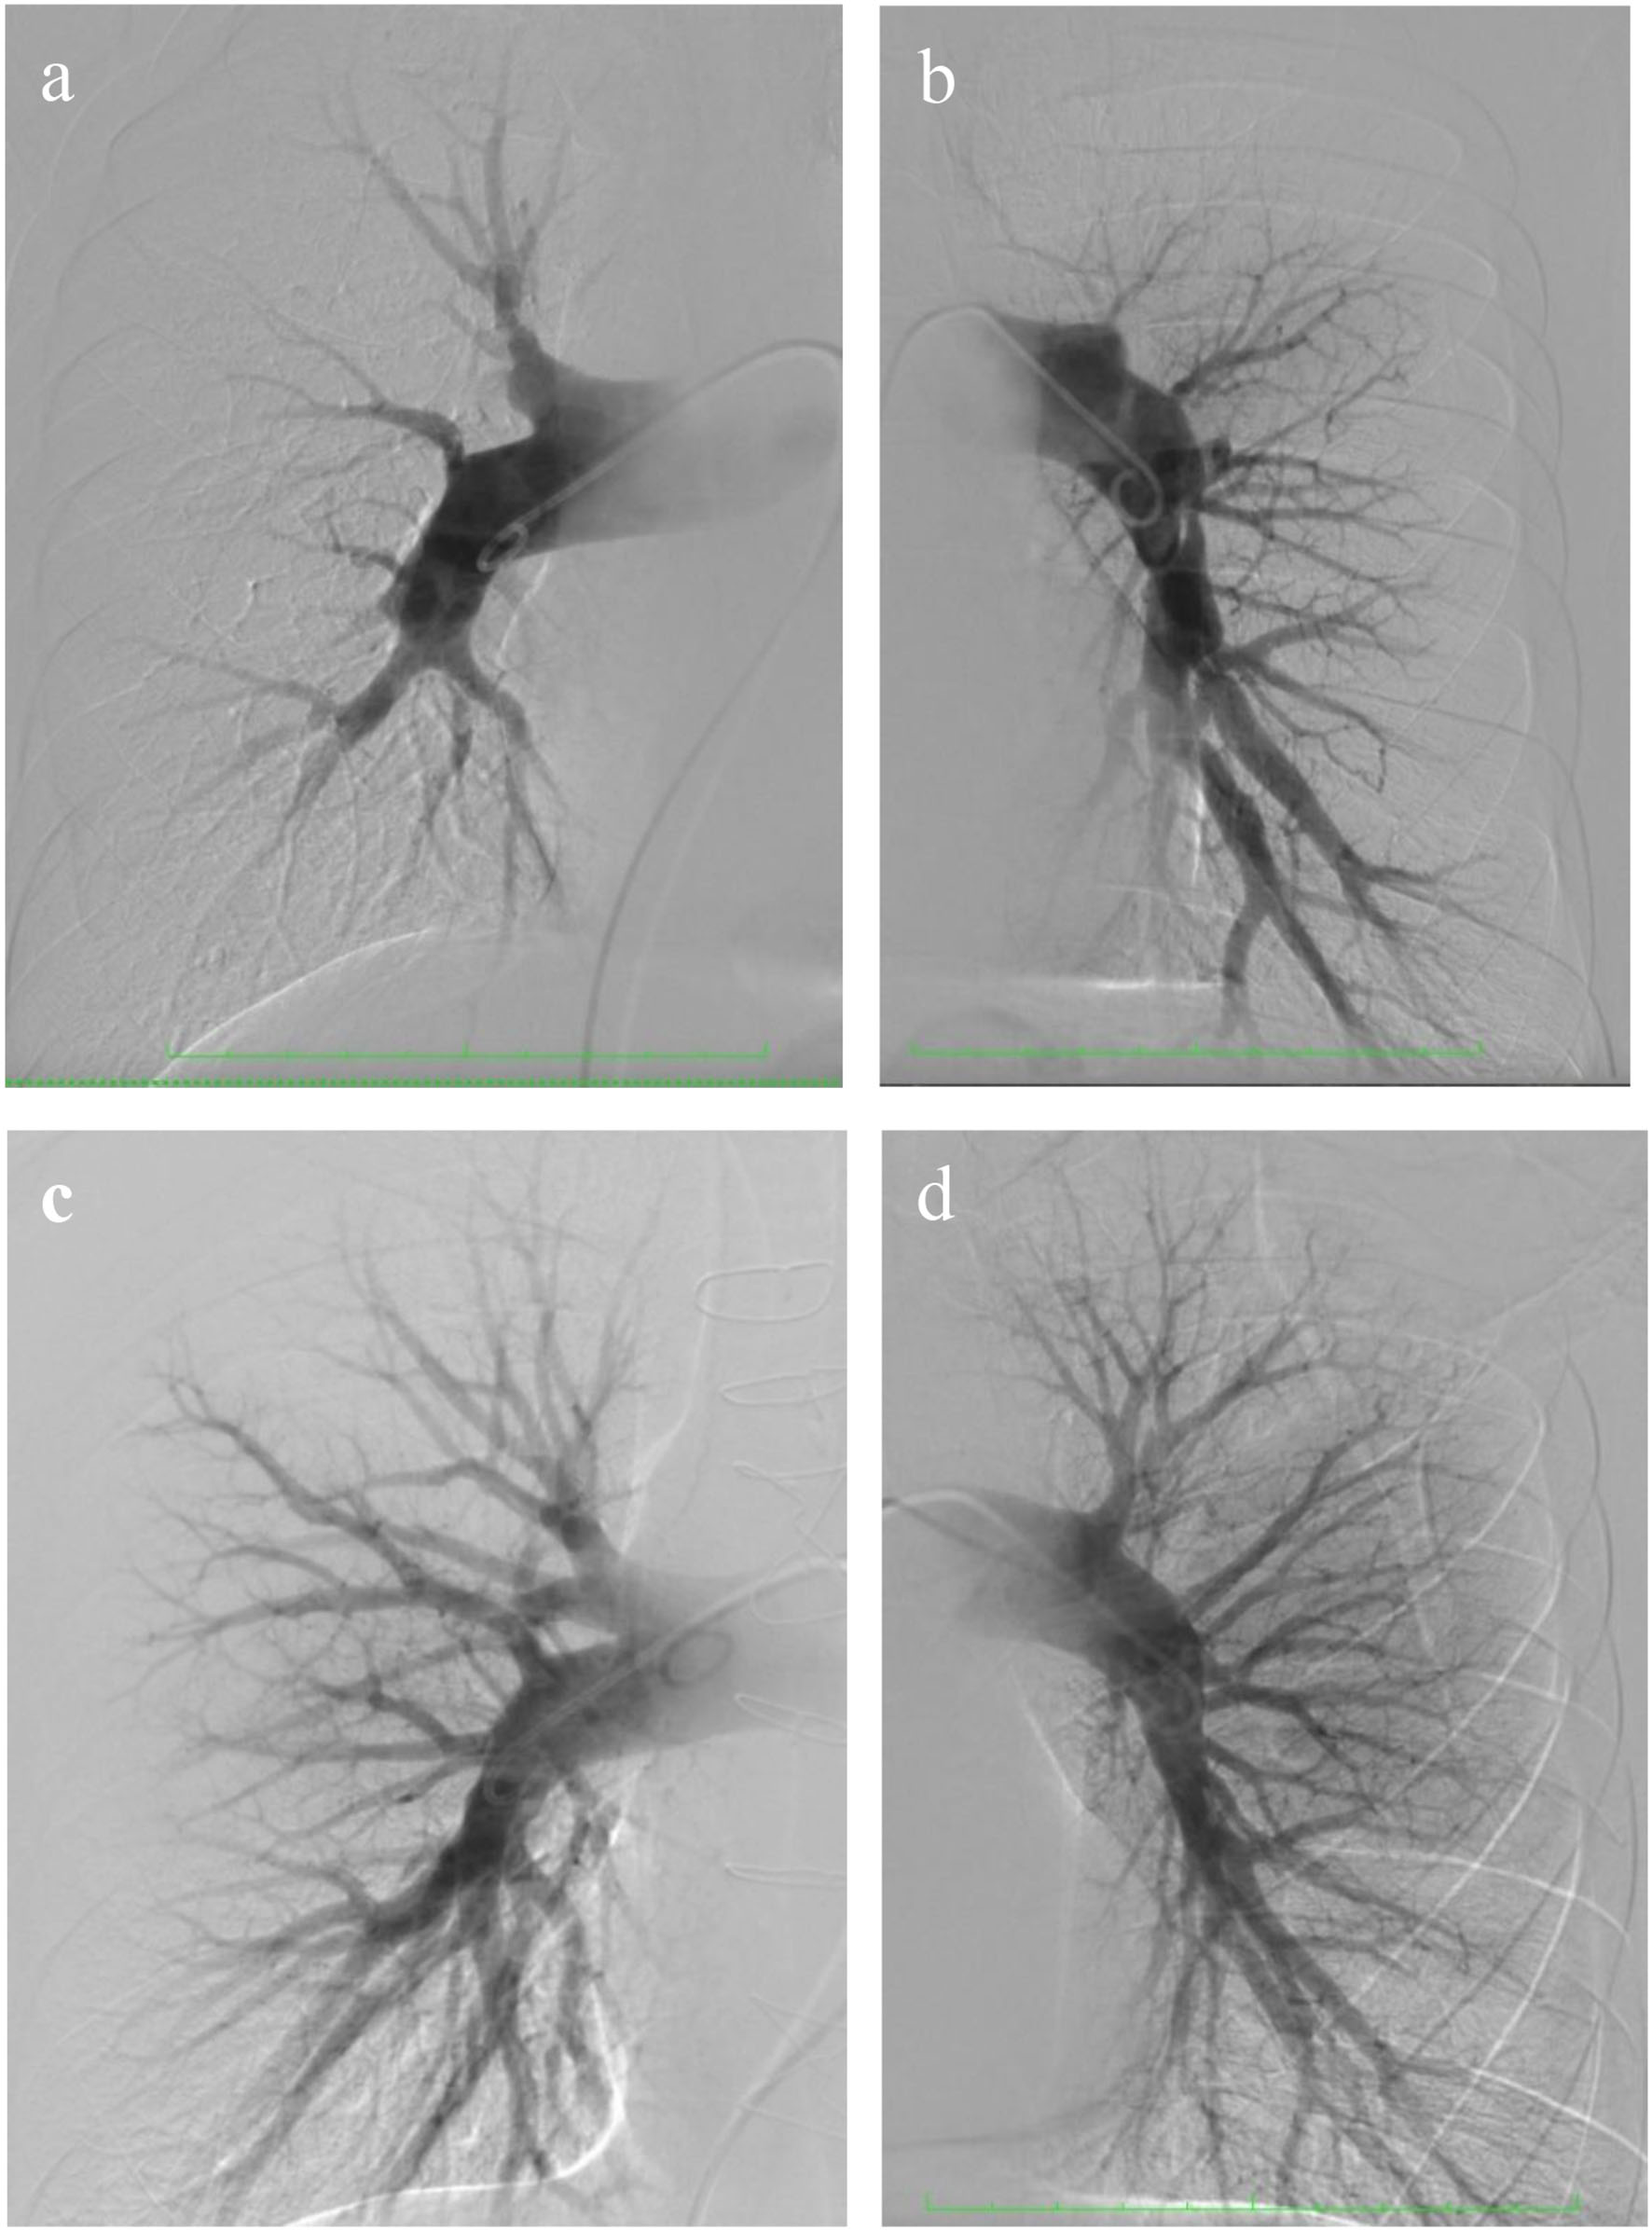

A 36-year-old man was referred to the Almazov National Medical Research Centre with a history of progressive heart failure (NYHA III functional class), chest pain, and the presence of severe pulmonary hypertension (PH) according to a transthoracic echocardiographic evaluation (TTE). The patient had a documented history of acute pulmonary embolism with a delayed diagnosis and initiation of anticoagulant therapy. TTE showed right atrial and right ventricle dilatation with preserved right ventricle function, left ventricle size, and function, and the estimated pulmonary artery systolic pressure was 120 mmHg (Table 1). Chest dual-energy CT-angiography and pulmonary angiography confirmed CTEPH (level II according to San Diego pulmonary endarterectomy disease levels) (Figures 1a,b). Right heart catheterization (RHC) defined precapillary PH: mean pulmonary artery pressure (PAP) of 59 mmHg, a pulmonary capillary wedge pressure (PCWP) of 13 mmHg, and a pulmonary vascular resistance of 7,98 Wood units. Riociguat treatment was started. Thrombophilia markers were tested, and antiphospholipid antibody syndrome was revealed as the main CTEPH risk factor. There were no data in favor of systemic lupus erythematosus or other systemic connective tissue diseases. Due to chest pain, selective coronary angiography was performed, and the LAD-MB was revealed. The length of the LAD-MD was ~25 mm, with left anterior descending artery stenosis in the systole reaching 70% (Figures 2a,c, arrowhead).

Figure 1. Pre- and post-operative selective pulmonary angiography. (a) Selective pulmonary angiography of the right pulmonary arteries identified: eccentric and extended stenoses in the segmental arteries A 1, 2, 4, 5, 6, 7, 8, and occlusion of A 3, 9, 10; (b) left pulmonary artery: occlusion of the upper lobe branch, roughness of the contours of the lower lobe branch, and eccentric and extended stenoses in the segmental arteries of the lingual segment and lower lobe; (c,d) selective pulmonary angiography after surgery.

The patient's health significantly improved and had no dyspnea at 8 months of follow-up. Selective pulmonary angiography demonstrated preserved blood flow over all pulmonary fields. No stenosis and occlusion of segmental branches were visible (Figures 1c,d). Coronary angiography found no local stenosis of the LAD artery (Figures 2c,d). The control RHC showed normalization of pulmonary hemodynamics with a reduced mean pulmonary artery pressure of 22 mmHg and an RVR of 1.7 WU (Table 2).